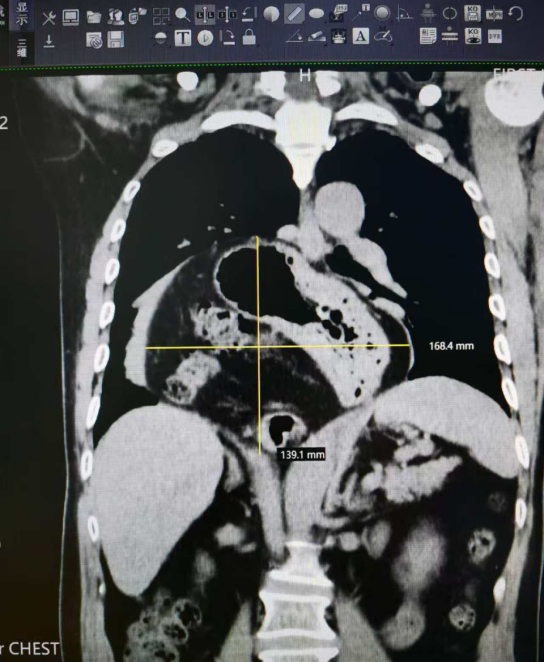

60岁的陆先生(化名),一周前突发胸痛、呼吸困难以及上腹部持续不适到佛山市第一人民医院急诊求诊,就诊后CT检查初步发现食管裂孔疝,随即被收入院。经过进一步的胃镜、上消化道造影、食管测酸测压等详细检查,令人震惊的复杂病情浮出水面——陆先生患有巨大食管裂孔疝伴胃扭转,疝囊大小约17cmx14cm。他的全部胃组织、横结肠及部分小肠,竟通过扩大的食管裂孔“跑”进了胸腔!这不仅严重干扰消化功能,还致使右肺组织被压缩,引发呼吸困难。更可怕的是,后续还可能出现食管溃疡、消化道出血、胃扭转坏死等致命风险,病情刻不容缓。